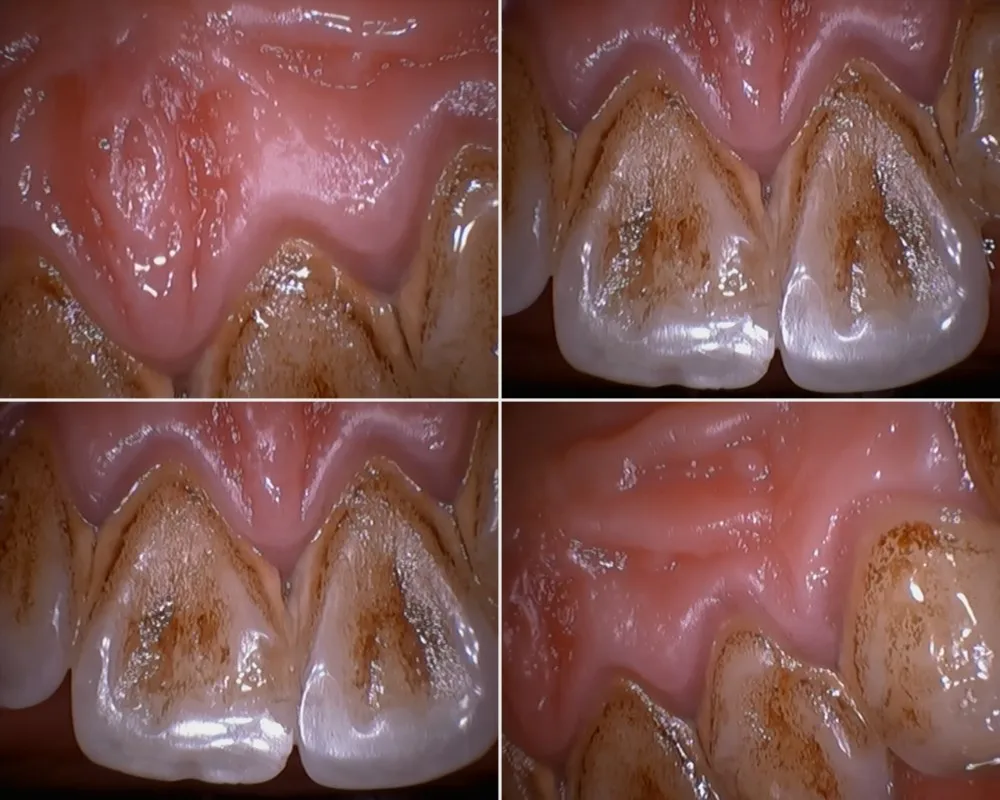

Blue light & white light intraoral camera for your option, blue light to check decayed tooth, dental plaque and dental calculas.

These photos we took from this NEW camera, the resolution is very good with zoom function.